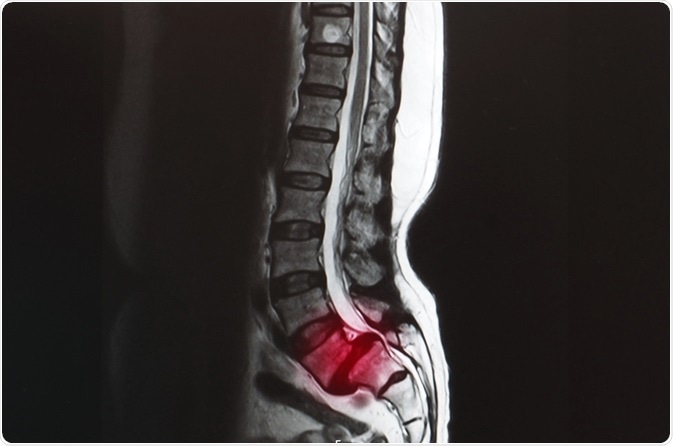

Spondylolisthesis

Spondylolisthesis. Image Credit: Yok_onepiece/Shutterstock.com